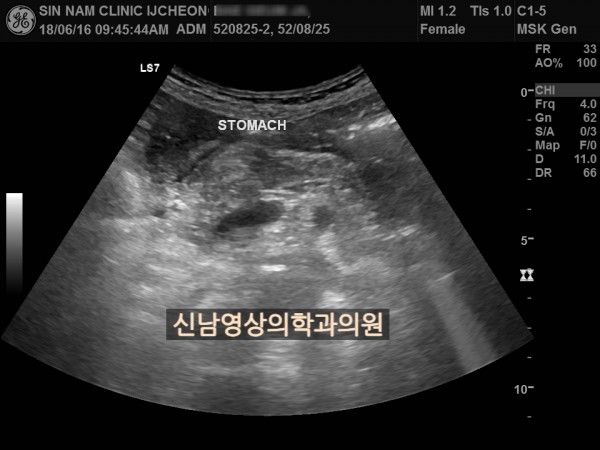

본 환자분은 변비가 지속되면서 좌하복부 통증이 있으셨던 분으로 본원에서 복부 초음파 검사를 진행하였습니다.

위암이나 대장암은 점막에서 발생하는 0기암은 초음파로 진단할 수 없지만 대장암이 점막을 넘어 근육층이나 장간막으로 퍼지게 되면 초음파 검사상 근육, 장간막 부위가 두꺼워지는 소견으로 나타나 발견하기도 합니다.